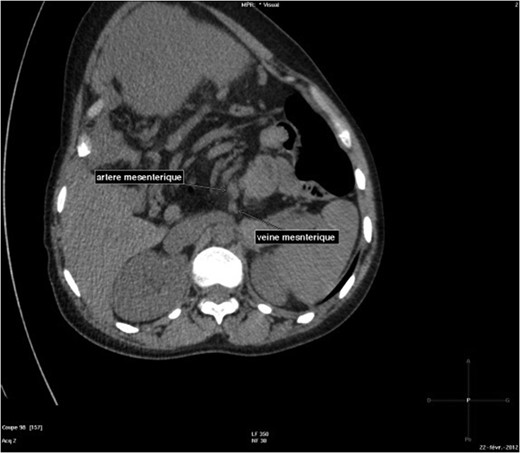

The abdominal-pelvic CT-scan showed a pre-splenic left position of the caecum and right colon, with no part of the colon on the right. The radiologist concluded that the patient was suffering from a complication of intestinal malrotation (IM) (Figs 1, 2, 3).

Abdominal-Pelvic CT-scan, non-contrast enhanced, in the sagittal plan, eleventh dorsal vertebra level.